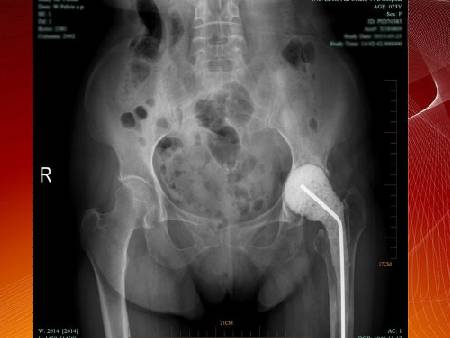

大家來(lái)找茬:請(qǐng)找出下圖中的兩條腿,有哪兩處不同?這是一張有問(wèn)題的腿的片子,問(wèn)題出在哪兒?這些問(wèn)題說(shuō)明身體什么問(wèn)題?敬請(qǐng)收看4月3日衛(wèi)生部中日友好醫(yī)院脊柱外科主任李中實(shí)教授,為您講述《健全骨骼 強(qiáng)韌有方》。